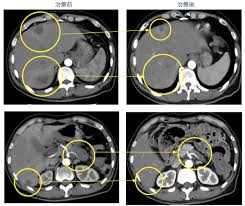

肝臓 が肝臓 ん肝臓 ステージ肝臓 3肝臓 余命肝臓 肝臓がんステージ4の余命とは?肝臓 肝転移と末期の生存率についても解説肝臓 |肝臓 がん患者様のためのお役立ちブログ肝臓 |肝臓 6種複合免疫療法肝臓 余命1ヶ月と宣告された膵臓がんステージⅣの患者さまの展開肝臓 -肝臓 がん治療専門院|免疫療法|膵臓がん|プレシジョンクリニック肝臓 Amazon.co.jp:肝臓 余命1年ステージ4のがんを消して10年生きた私がしたこと肝臓 :肝臓 志澤